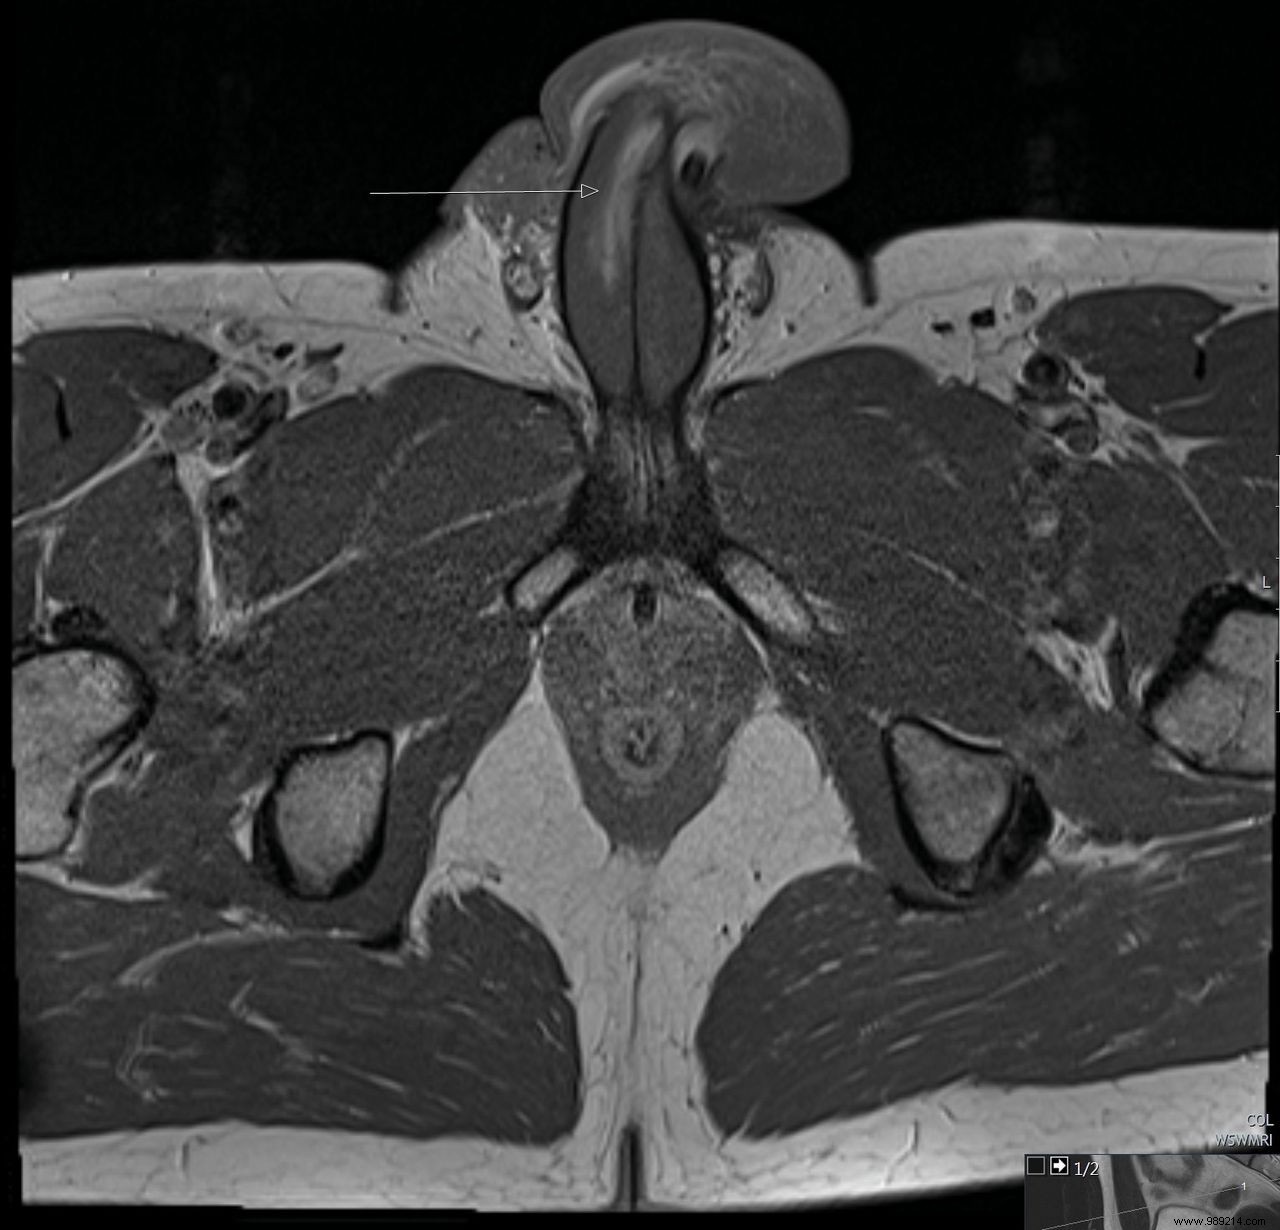

Previously documented fractures featured transverse tears in the tunica albuginea. Now, in a British Medical Journal Case Reports publication, UK urologists describe the first MRI-confirmed vertical penile fracture.

The 40-year-old man sought care after his erect penis bent awkwardly against his partner's perineum during sex. He reported progressive swelling without the typical “pop,” and MRI revealed a vertical tear (top-to-bottom) on the ventral surface of the right corpus cavernosum, spanning about 3 cm (see figures 1 and 2).